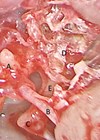

Endoscopic excision of cholesteatoma

In this article Vikranth Visvanathan describes an exciting development on the use of endoscopic technology in complex otological practice. Transcanal endoscopic ear surgery (TEES) is rapidly evolving as a recognised method of addressing middle ear and mastoid pathology. Since its...